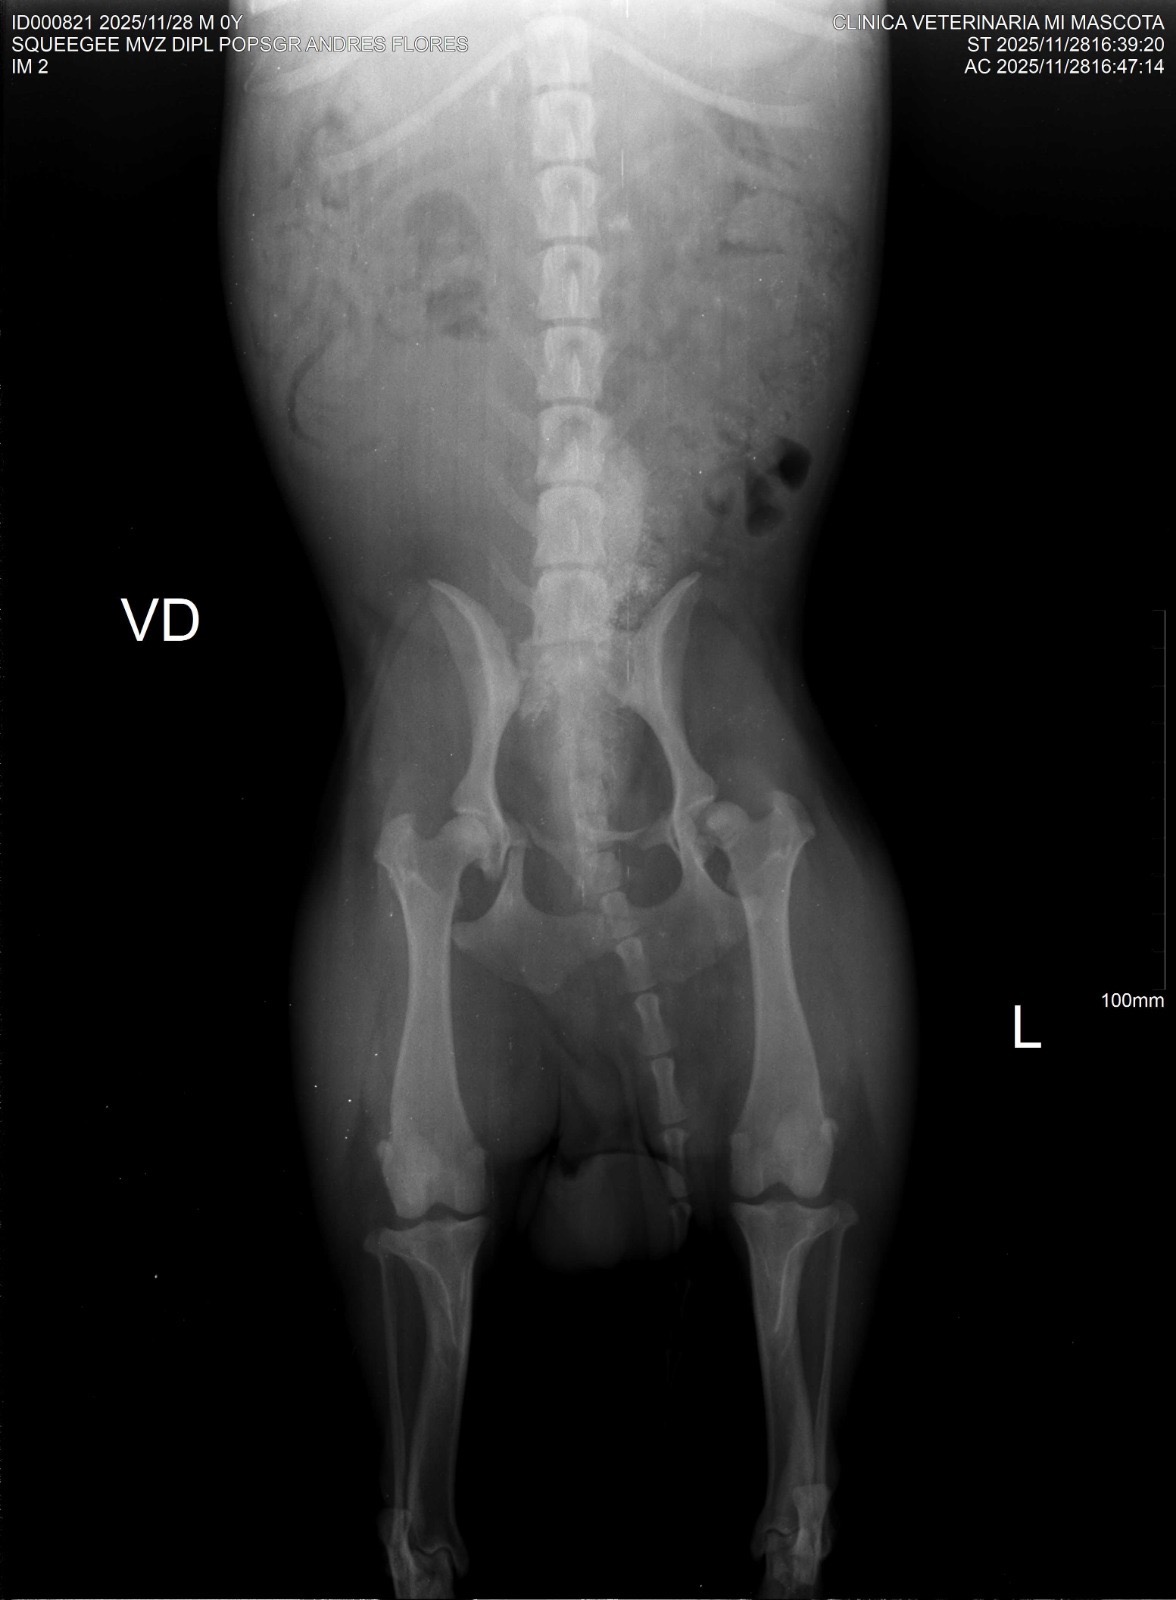

to the local vet who did X-rays, blood work and an ultrasound. This poor baby has two pelvic fractures, one sacroiliac fracture, one hip fracture one ischium fracture and a rib fracture he is also heartworm positive. We were referred to a surgeon in a different state for a consult, today we drove him to the surgeon who miraculously confirmed there is no internal bleeding, his bladder and liver are intact, his lung was not punctured by the rib and the ultrasound revealed no mature worms in his heart or arteries. He will be able to make a full recovery with surgery and treatment. Unfortunately logistics aren’t working in our favour. The surgeon is not confident doing repairs of the pelvis and won’t perform the surgery on his hip for another month then there is another month of recovery before he would be cleared to fly. The costs to board the dog at the vet awaiting the surgery and for the recovery, the medication, the cost of additional flights and the cost of the surgery itself quickly add up to nearly the same costs of treatment in Canada. Matt and I we are already $1000 deep trying to save this little guy who we’ve lovingly named Squeegee after we squeegeed this little pancake off the road. We are hoping to raise funds to bring this little guy home with us for treatment in Canada on Dec 4th. I have been in touch with our regular vet who has confirmed these injuries require surgery. The anticipated costs will range from $4000-8000. Anything you are willing to contribute will help, we will cover the rest. In the event there were excess funds not used for his care we would donate to an animal rescue in Mexico that helps other street pups like Squeegee.